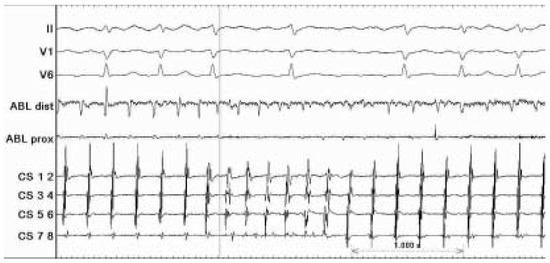

Case description A 70-year-old former athlete complained about a twenty-year history of paroxysmal atrial fibrillation with onset at rest and during the night, which became persistent in the last three years [...]